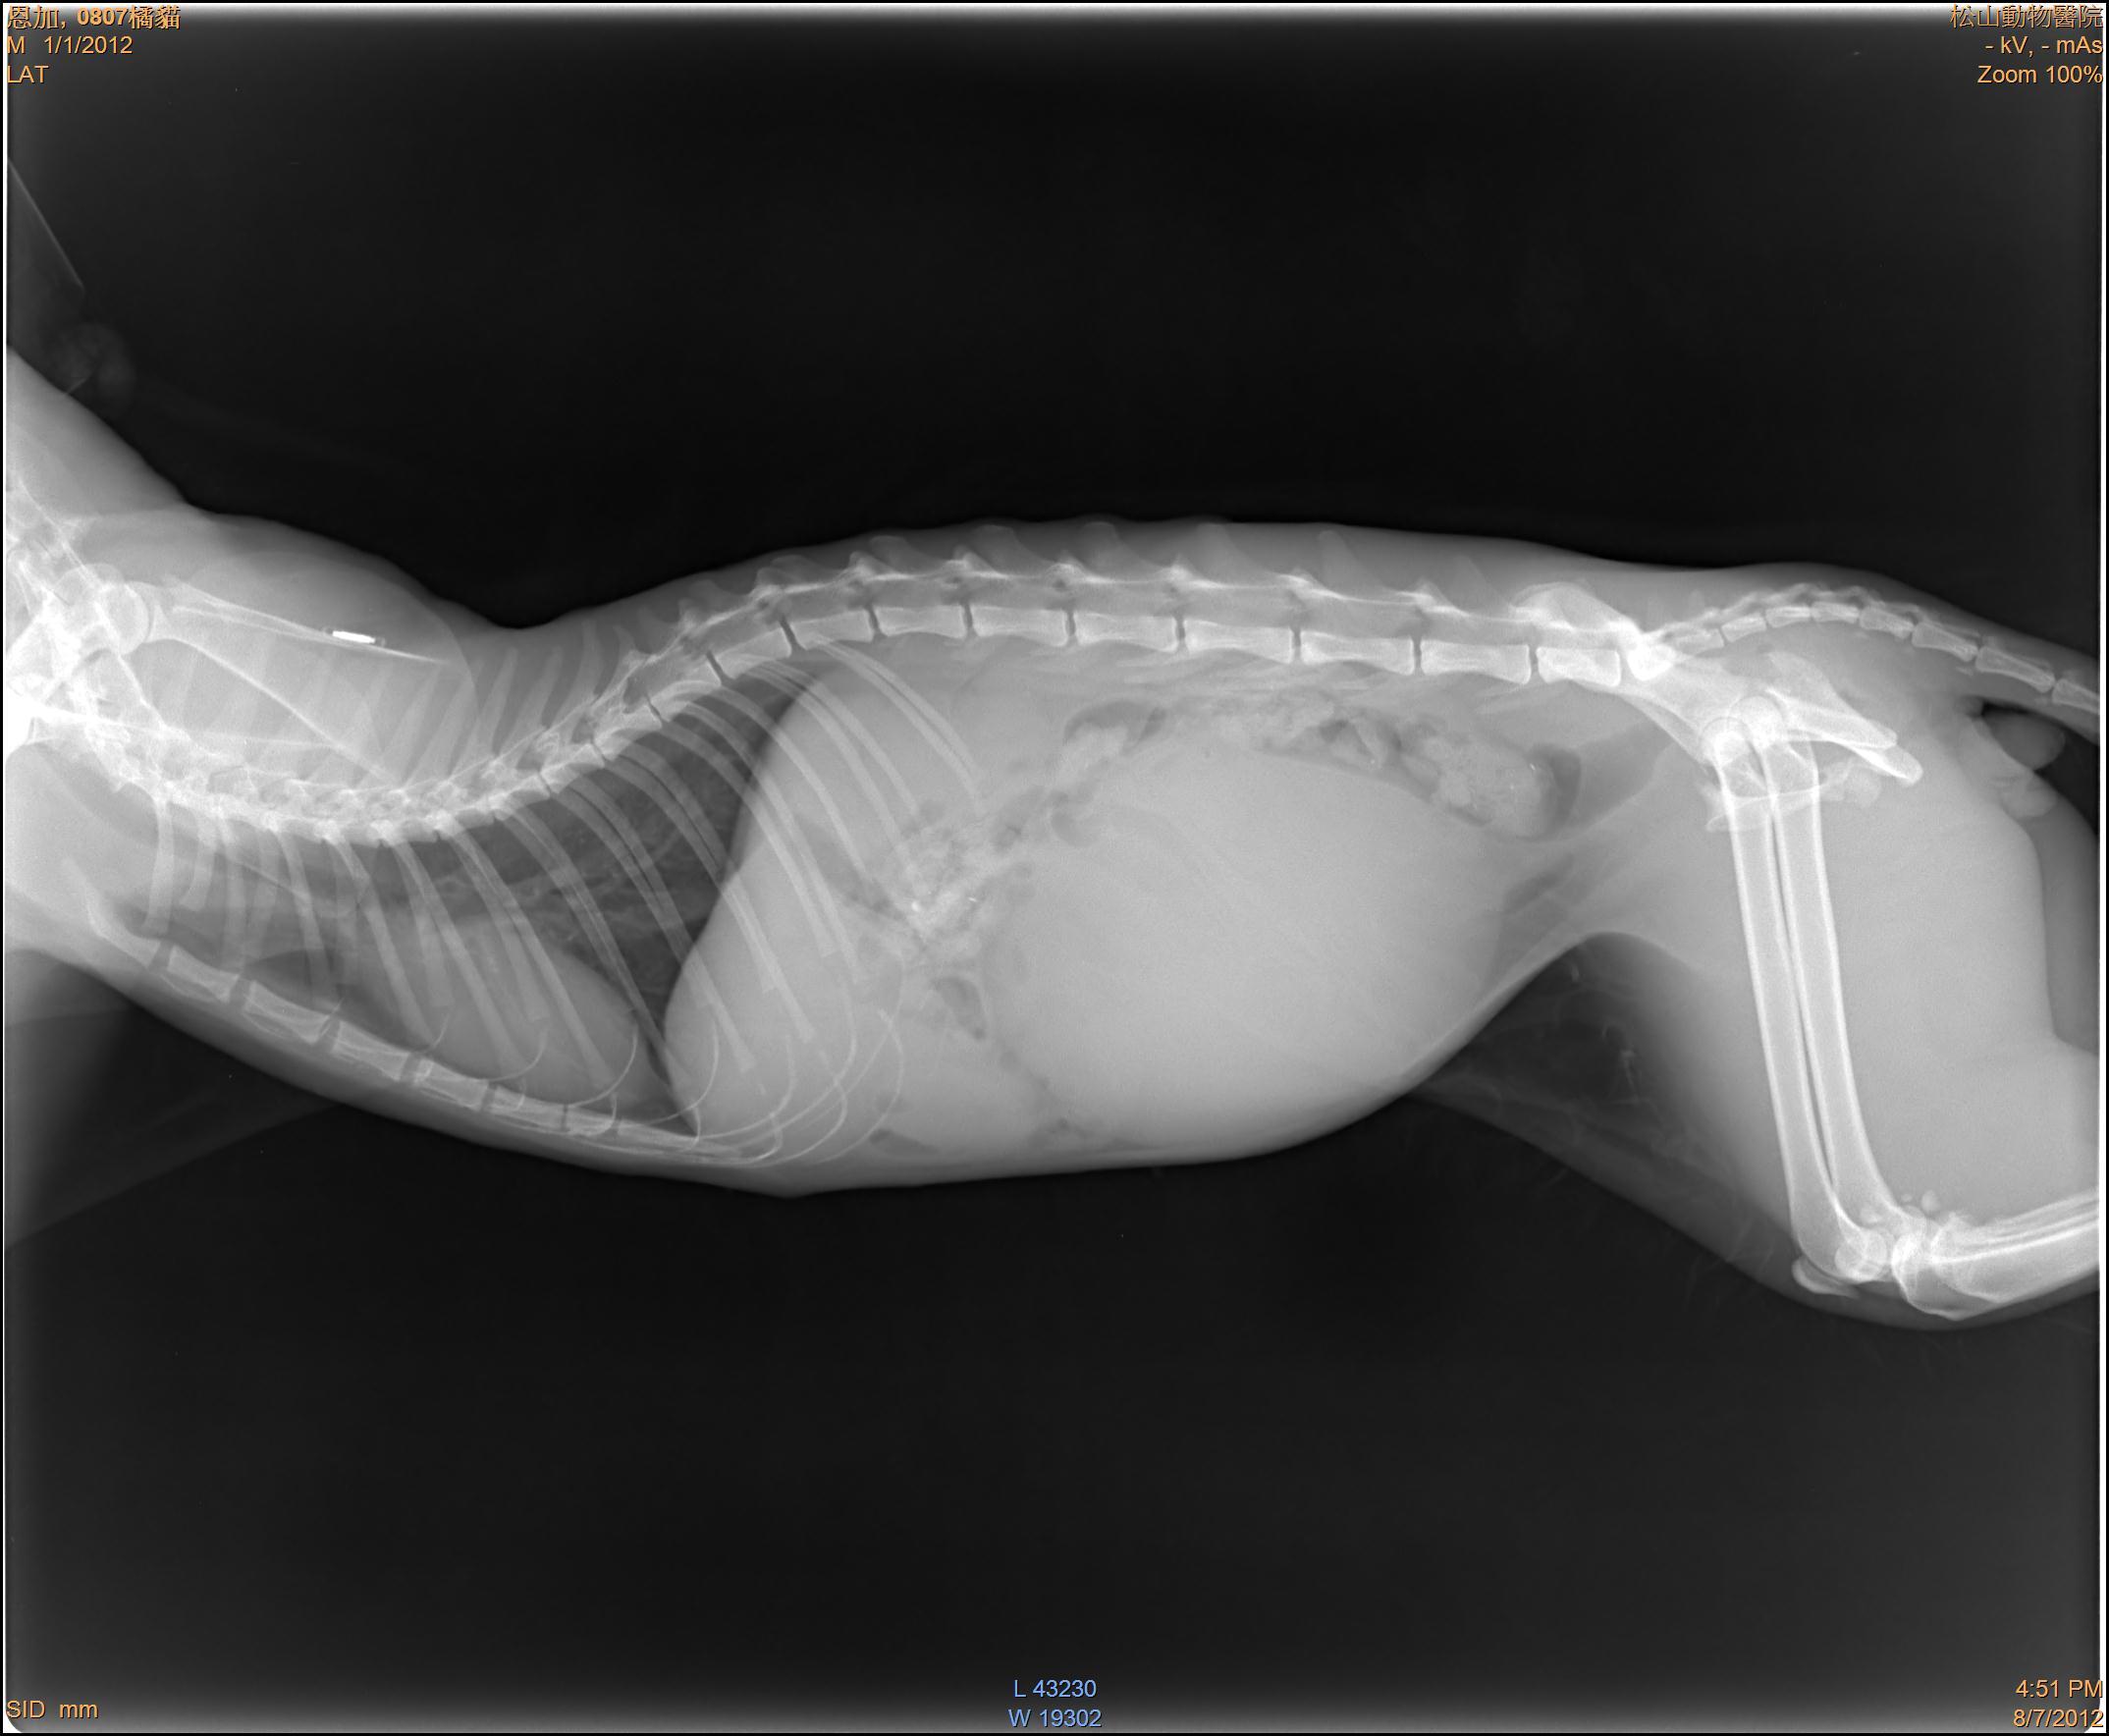

主題: 車禍骨盆腔骨折黃虎斑貓(參天) 申請者姓名: 敏大哥 花色: 申請日期: 2012-09-20 21:06:33 申請者部落格: 申請者臉書網址: 所在縣市/合作醫院: 台北市/恩加動物醫院 治療費用: 3700元 需求人數: 9人 已結案 (2013-06-27 13:37:14) 報名人員: Summer(已付款)、Summer(已付款)、mandy(已付款)、Tiffany Chen(已付款)、小冬(已付款)、kim(已付款)、鴻淵(已付款)、小麥、小麥、有貓真好(已付款)、姍珊(已付款)、 候補人員: 動物病情說明: 民眾通報車禍路倒貓,是我以前TNR的貓咪,先在動物醫院做初步維持生命跡象,而後由版主轉往其他醫院做進一步的治療。